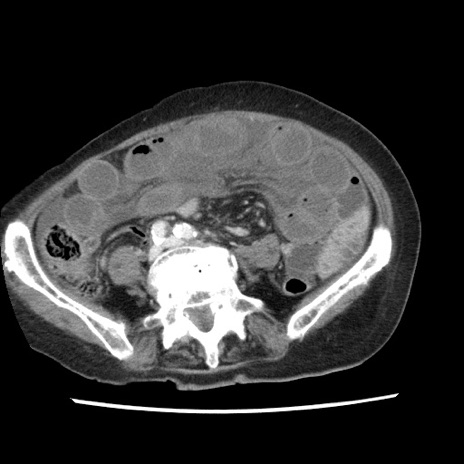

【症例】80歳代女性

【主訴】腹痛

【現病歴】8時間前から腹痛あり来院。

【既往歴】糖尿病、脂質異常症、子宮体癌にて子宮全摘術

【身体所見】意識清明・会話良好だが腹痛で苦悶様、全腹部にわたって反跳痛と圧痛あり

【データ】WBC 13600、CRP 0.14、LDH 224、CK 90